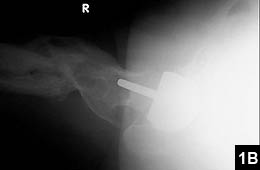

An uncommon, but useful indication for hip resurfacing is for patients with proximal femoral deformity, in whom a total hip can be difficult if not impossible (Figure 1). More commonly, suboptimal anatomy is an issue, as with patients in whom even the smallest stem requires reaming, which puts patients at long-term risk for stem fracture (Figure 2). Conversely, a large canal presents problems for implanting a cementless stem (Figure 3).

Figure 1: Preoperative radiograph of a patient with post-traumatic arthritis decades after sustaining a fracture in an airplane accident (A). Postoperative radiograph after successful total hip resurfacing confirms standard total hip arthroplasty would have been a massive undertaking (B).